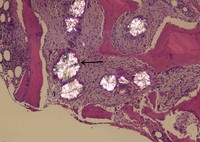

• NRBC

Najmaldin Saki, P...

Nucleated Red Blo...